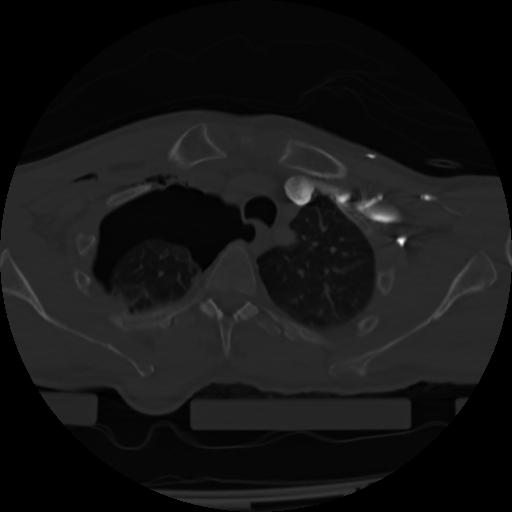

21 ANGIO,CE,Axial,3.0,ANGIO,,